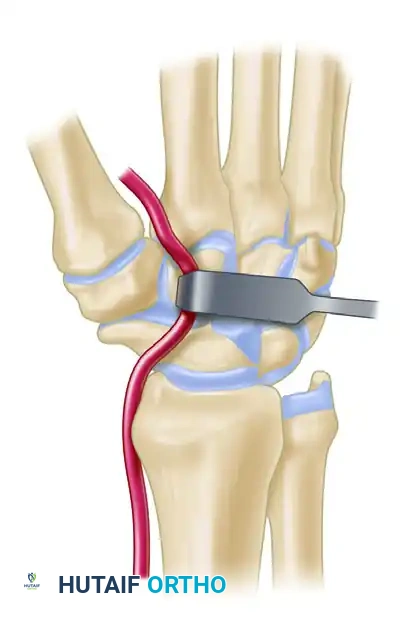

- Metacarpal Tunnel: Create an extraarticular bone tunnel from the dorsal base of the metacarpal to the volar beak apex.

- Vector: The tunnel must be in a plane strictly perpendicular to the thumb nail.

- Starting Point: Start just distal to the dorsal base of the metacarpal, between the extensor pollicis brevis (EPB) and extensor pollicis longus (EPL) tendons.

- Exit Point: The volar beak of the metacarpal. Do not breach the articular surface.

Figure: Gouge tract created in the sagittal diameter of the metacarpal, emerging at its volar beak. A small branch of the radial nerve is retracted volarly.

Intraoperative view demonstrating the creation of the metacarpal tunnel.